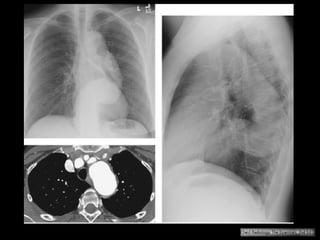

Complicações do aneurisma aórtico

Ruptura é a complicação mais grave;

Taxas de mortalidade entre 70-94%;

Mortalidade no tratamento eletivo: 4%;

Sinais de ruptura: descontinuidade de uma

calcificação circunferencial, presença de crescente

periférico com densidade aumentada, parede

posterior indistinta e extravazamento de meio de

contraste;

O sinal do crescente hiperdenso na parede da aorta

representa hematoma agudo com sangue contido

no interior do trombo do aneurisma;

Diagnosticado melhor na fase sem contraste;

Ruptura da aorta: infiltração da gordura

mediastinal, hemomediastino, hemopericárdio ou

hemotórax;

Formação de fístula: 3ª. Porção do duodeno é o

segmento mais afetado (fístula aortoentérica);

Ruptura: extravazamento do contraste e hemotórax

Haaga JR, Dogra VS, Forsting M, et al. TC e RM uma abordagem do corpo humano completa. Editora Mosby-Elsevier,

2009.